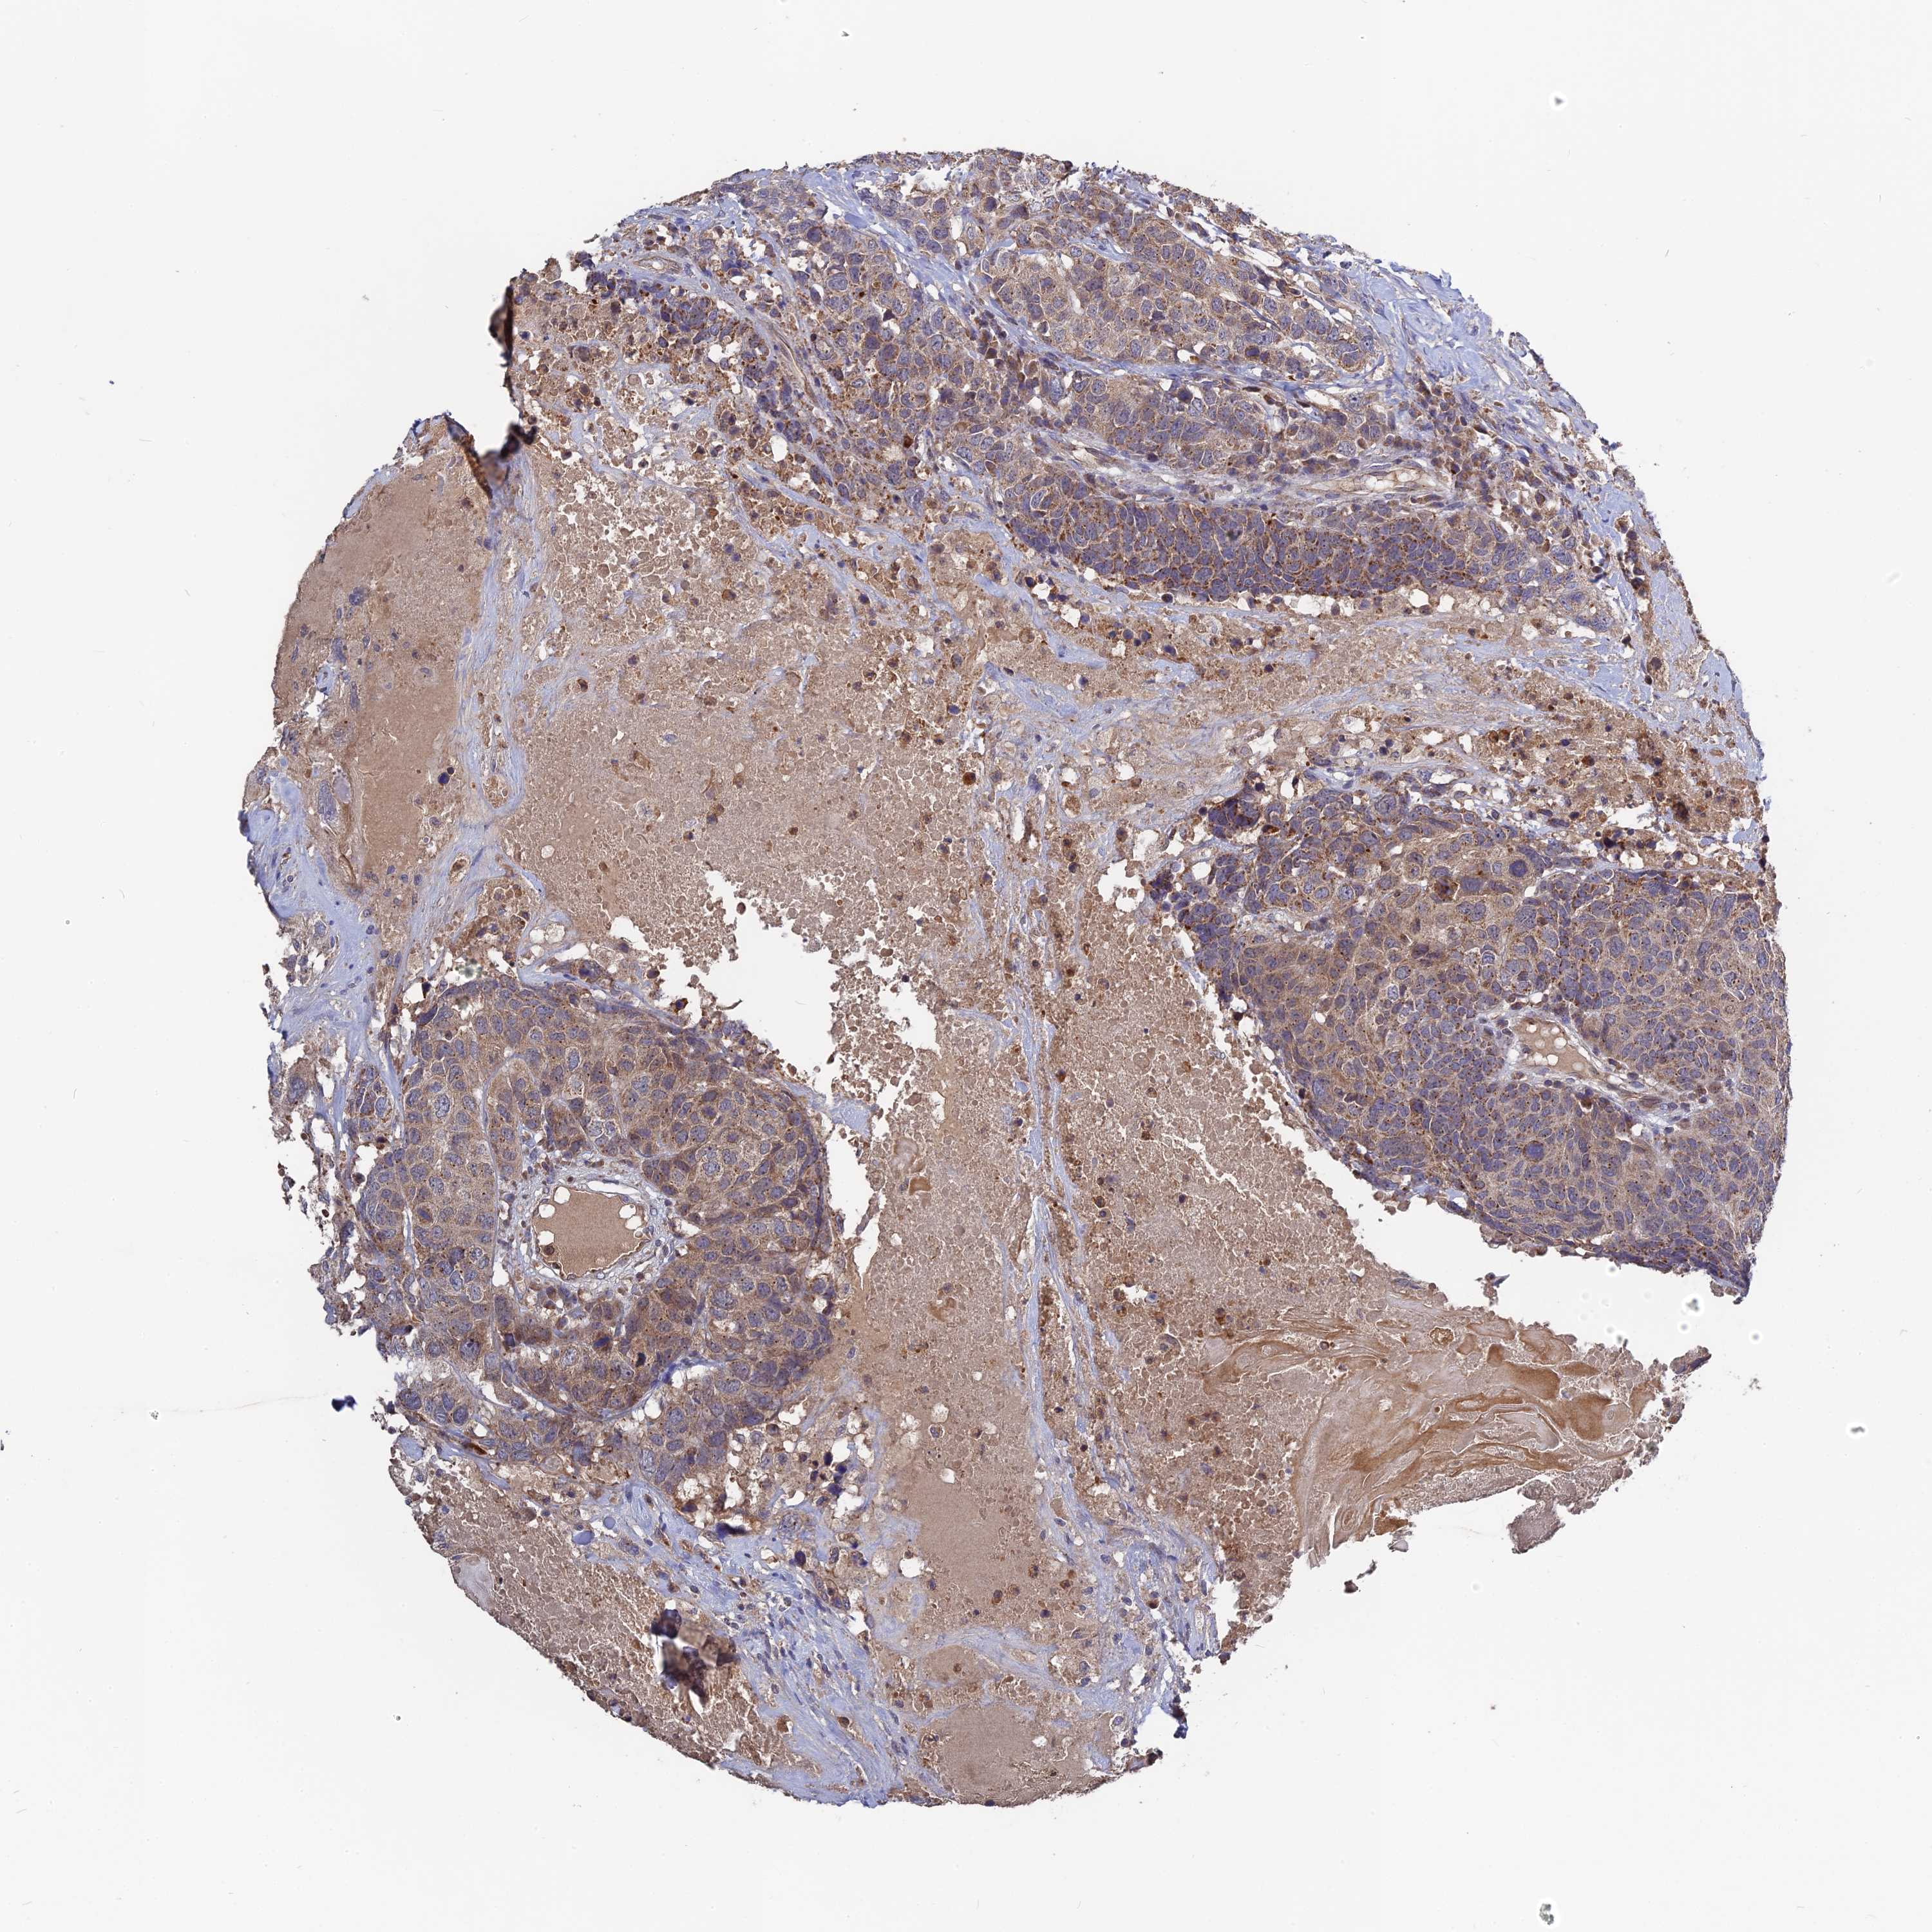

HEAD AND NECK CANCER - Protein expressioni

A mouse-over function shows sample information and annotation data. Click on an image to view it in a full screen mode. Samples can be filtered based on level of antibody staining by selecting one or several of the following categories: high, medium, low and not detected. The assay and annotation is described here.

Antibody stainingi

Antibody staining in the annotated cell types in the current human tissue is reported as not detected, low, medium, or high, based on conventional immunohistochemistry profiling in selected tissues. This score is based on the combination of the staining intensity and fraction of stained cells.

Each image is clickable and will lead to virtual microscopy that enables deeper exploration of all samples and also displays staining intensity scores, fraction scores and subcellular localization as well as patient and tissue information for each sample.

Antibody HPA042620

Staining

High

Medium

Low

Not detected

Intensity

Strong

Moderate

Weak

Negative

Quantity

>75%

75%-25%

<25%

None

Location

Nuclear

Cytoplasmic/membranous

Cytoplasmic/membranous,nuclear

Adenocarcinoma, NOS

Squamous cell carcinoma, NOS